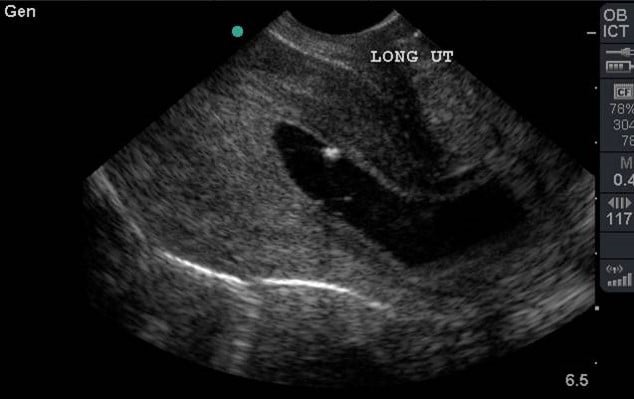

- Illustration 8. Image of transvaginal sagittal/longitudinal view. Notice hyperechoic (bright) endometrial stripe.

- Fan the probe anteriorly and posteriorly to view the entire uterus (Video 5).

- Definitive evidence of an IUP is a gestational sac containing a yolk sac (YS) in two planes within the endometrium which usually occurs around 5-6 weeks gestational age.3,6 (Video 6 and 7)